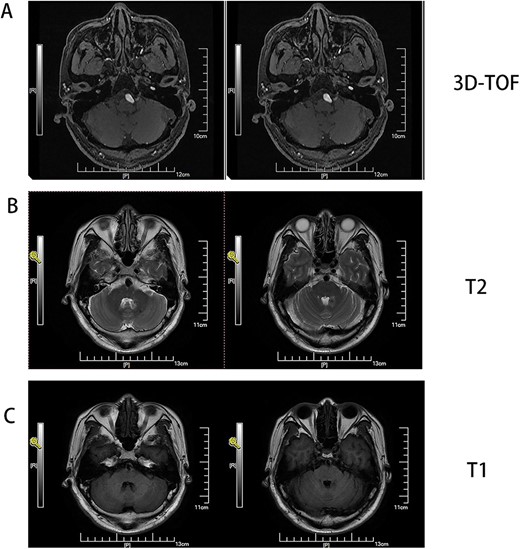

Male, AA, 44 years old, admitted in July 2022 with recurrent pain on the left side of the maxillofacial region for ~1 year. In the last 6 months, the dose of carbamazepine was increased to 300 mg three times daily, but the control of facial pain was still unsatisfactory, so the patient and his family numbers requested to be hospitalized for surgery. The patient had a history of hypertension for ~15 years. The maximum blood pressure was ~200/120 mmHg. The nifedipine controlled-release tablet was used to control his blood pressure by 30 mg daily, which is maintained at ~140/80 mmHg. The neurological examination on admission was unremarkable. TN was assessed as grade V according to the Bar row Neurological Institute classification. Magnetic Resonance Imaging (MRI) of the head suggests small ischemic focus in the pons and cerebellum; marked extending of the basilar artery (Fig. 1A–C). To clarify the etiology, doppler ultrasound of the carotid and vertebral arteries bilaterally revealed no atheromatous plaque or hemodynamics abnormalities. An electrocardiogram and cardiac function and cardiac ultrasound were performed. The results were normal. Biochemical tests for blood cell count, liver function, kidney function, and glucose test revealed no abnormalities. The Digital subtraction angiography (DSA) was given to the patient (Fig. 2A and B). Antiplatelet aggregation therapy with a combination of clopidogrel and aspirin was used before operation. The DSA displayed the VBD, the VBD was length 2.5 cm and width 9 mm, its path was tortuous and deviated to the left. Normal blood flow in the middle venous phase of the imaging was normal. Stent-assisted interventional embolization was chosen. A suitable coil was selected to form basket by EV3 (20 mm*50 cm, Medtronic, USA) and the stent catheter was withdrawn and repositioned through the coil into the right posterior cerebral artery. Release stent 1: LEO (5.5 mm*60 mm, LEO, USA), then choose the appropriate ring (14 mm*30 cm, 13 mm*30 cm, 12 mm*30 cm, 10 mm*30 cm, Taijie Weiye, China) to occlude the dilated artery (Fig. 3A). Postoperatively, we scanned the Computed Tomography (CT) (Fig. 3A), the TN was completely relieved, but there was residual left-sided facial palsy with a House-Brackmann grade IV and a grade III right limb muscle strength. Systematic treatment was operated at the rehabilitation unit, once the condition was stabilized. At 3 months post-operative follow-up the patient showed significant improvement in muscle strength in the right limb, with muscle strength grade V− and significant improvement in facial palsy, which was graded House-Brackmann grade II.

(A) MRI 3D-TOF(3 digital- time of flight), (B) MRI T2, C:MRI T1. Basilar trunk dilation up to 9 mm of diameter deviated path to the left side responsible of medulla compression.